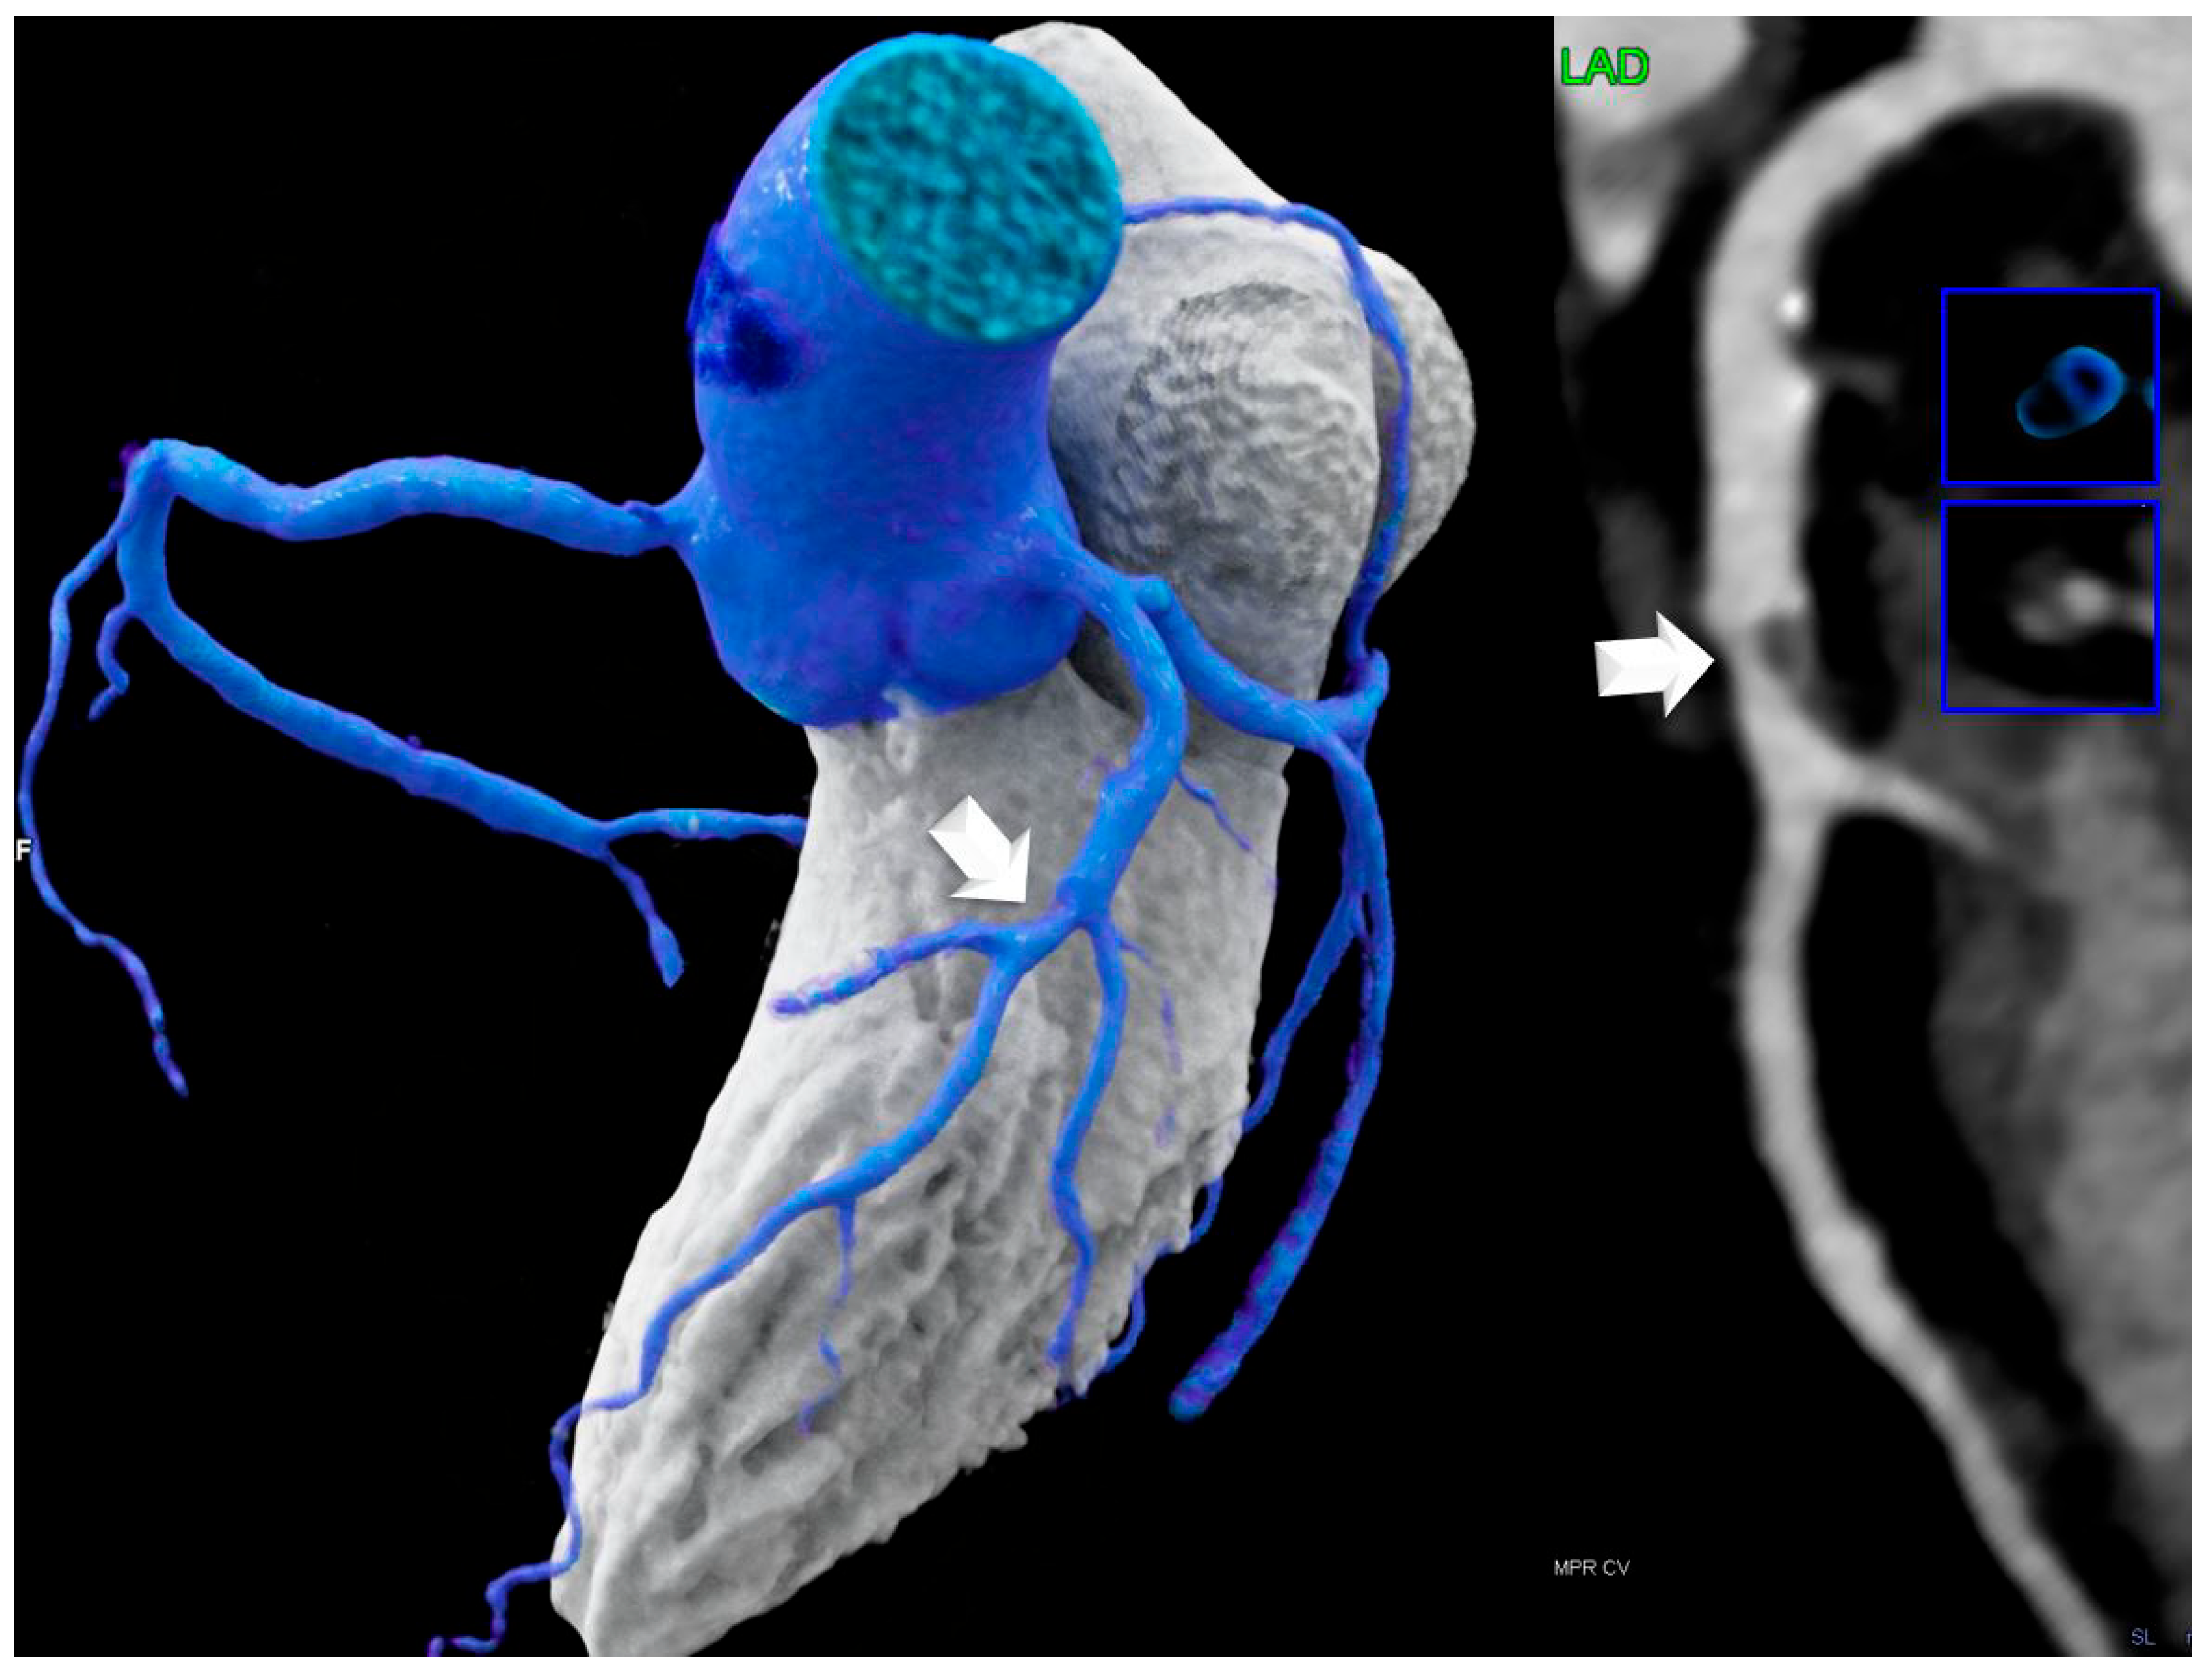

- Lipomatous hypertrophy of the interatrial septum (LHIS): This is defined as a mass-like lipomatous tissue infiltration of the entire interatrial septum from cranial to caudal, sparring the fossa ovalis, with a “dumb-bell” configuration with >than 5 mm width.The maximal width was identified on axial images and measured with a digital caliper. The maximal length was defined as the distance from the anterior to the posterior borders.

- Non-coronary CTA parameters: CT density of LHIS was measured. A circular region-of-interest (ROI) was placed in the area of maximal LHIS width, and CT density (HU) was measured. LHIS width and length were also measured.